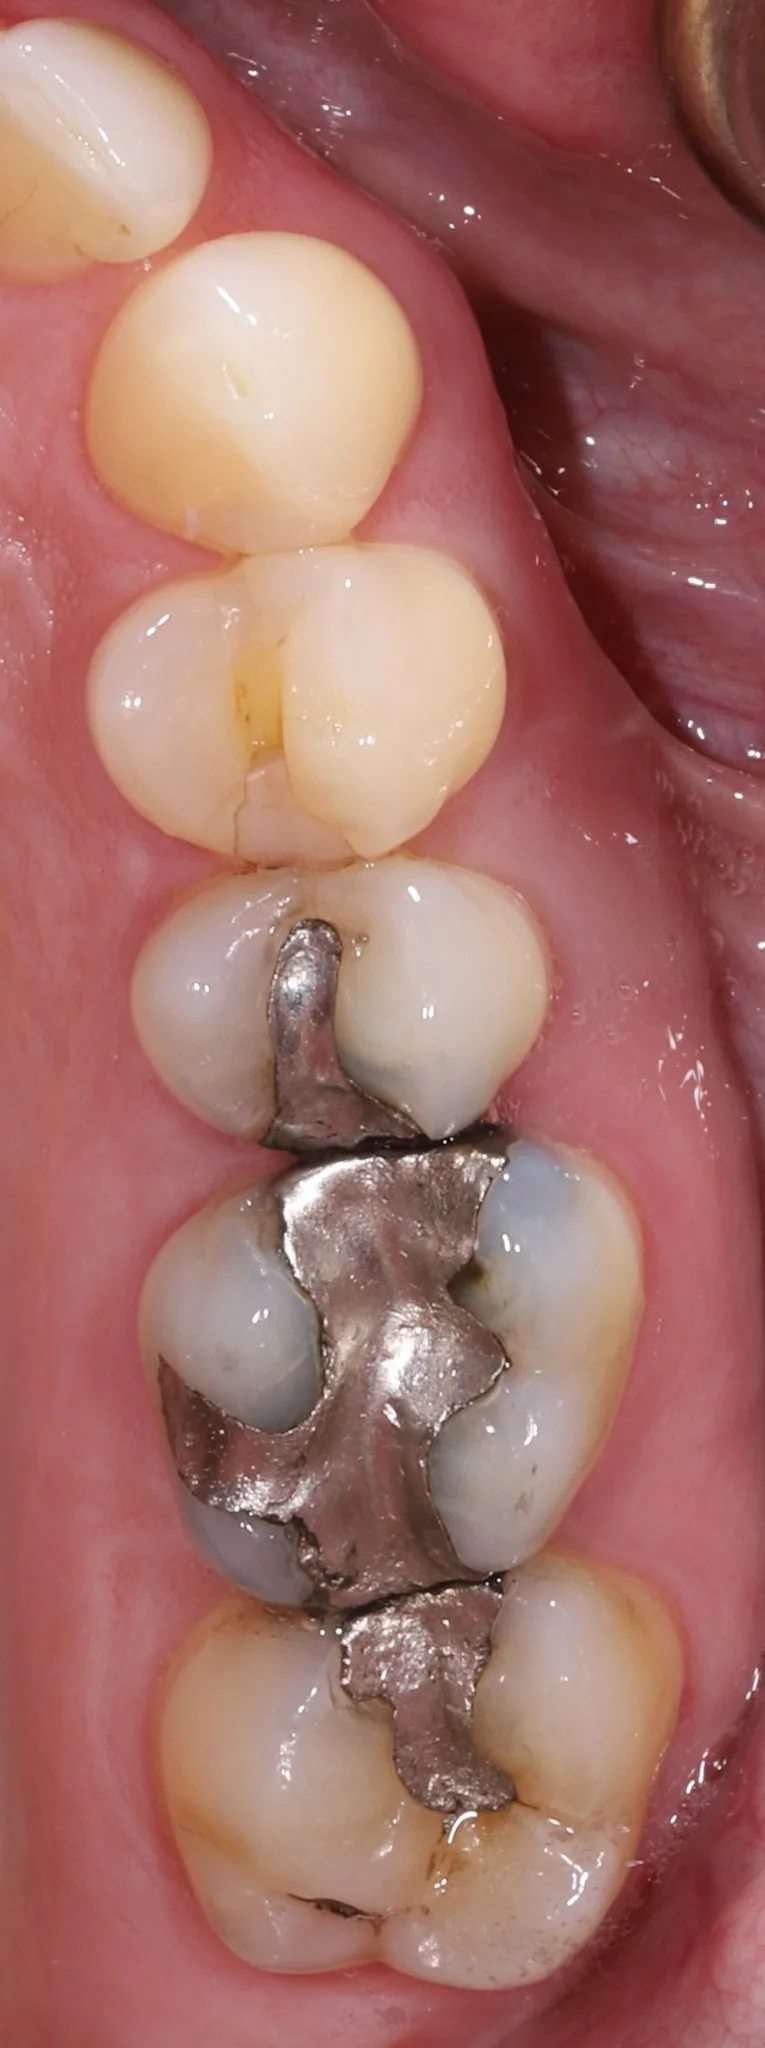

Close-up of a person's molar teeth with leakage, cracks and decay.  Prior to restorative treatment.

Before: Large silver fillings with leakage and cracks

Close-up of a person's molar teeth restored with gold and composite resin.

After: Gold partial coverage restoration to protect from further fracture